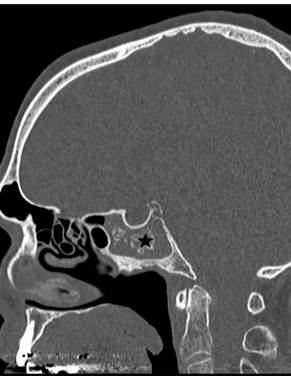

(Figure 1) After consultation with an otolaryngologist, a trial of prednisone and antibiotics was instituted with no change in symptoms. A follow-up CT scan showed no change in the sphenoid sinus lesion but also revealed intralesional calcification further supporting the diagnosis of mycetoma.

Figure 2. Axial (A) and sagittal (B) CT images showing calcified material (black stars) filling the sphenoid sinus suggesting the diagnosis of mycetoma.

(Figure 2) It was unclear whether the isolated fourth nerve palsy was related to the sphenoid sinus infection.